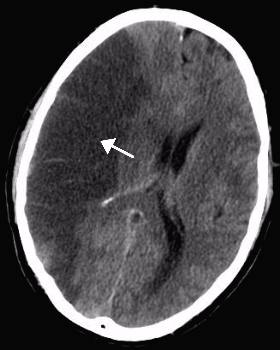

<여기서 잠깐> 뇌경색 혹은 뇌출혈 후에는 뇌부종이 온다. 우리 몸은 정상이 아닌 상황에 대한 염증 반응을 일으키기 때문이다. 우리가 팔다리에 타박상을 입거나, 열상을 입으면 수상 부위가 부어오르는 것과 마찬가지이다. 다음 사진은 정상 뇌와 뇌경색이 발생하여 뇌부종이 생긴 뇌의 CT 사진이다. 좌측의 정상 뇌에 비하여 우측 사진은 뇌경색에 동반된 뇌부종으로(화살표) 뇌가 전반적으로 오른쪽으로 밀려 있는 것을 관찰할 수 있다.

뇌부종이 무서운 이유는 뇌는 단단한 두개골에 싸여 있기에 압력이 밖으로 분산되지 못하고 부어오른 만큼 뇌압을 증가시켜 뇌를 압박하기 때문이다. 이러한 뇌부종은 뇌의 위축이 하나도 없어 두개골 내 공간이 적은 젊은 사람에서 더 위험하다. 본문에서 과장님이 응급수술을 준비하라고 이야기한것 역시 같은 맥락에서 두개골을 제거하여 뇌압을 낮추는 수술이 필요할 가능성이 있기 때문이다.